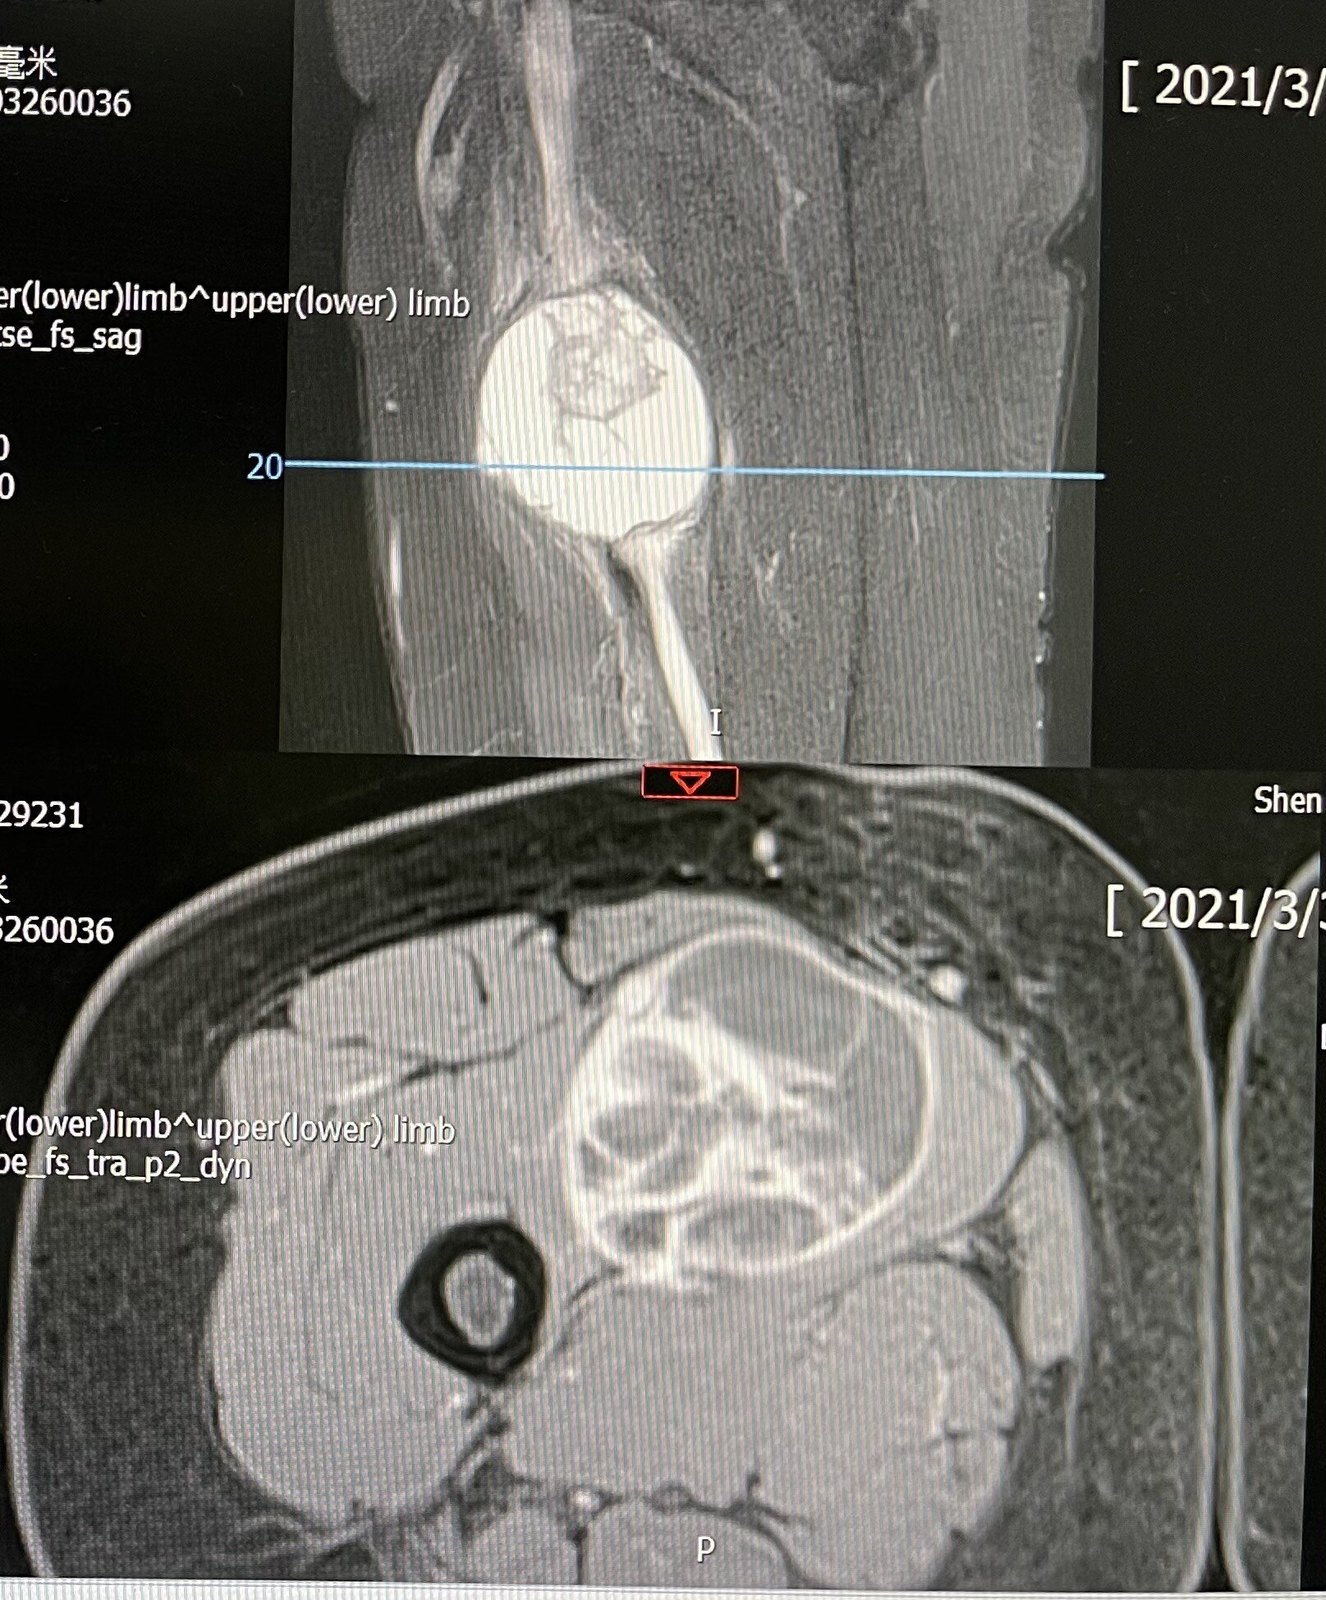

2. 影像学:B 超、X 线、CT、MRI 等。四肢软组织肉瘤首选 MRI 检查而非CT。高危患者应行胸部 CT 以排除肺转移。同时应检查区域淋巴结情况。